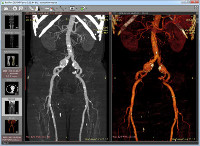

| 3D MPR (oblique multiplanar reconstruction) with MIP (maximum intensity projection), MinIP (minimum intensity projection) and Avg (average) modes |

| 3D VR (volume rendering) |

| GPU acceleration for 3D VR and 3D MPR/MIP5 |